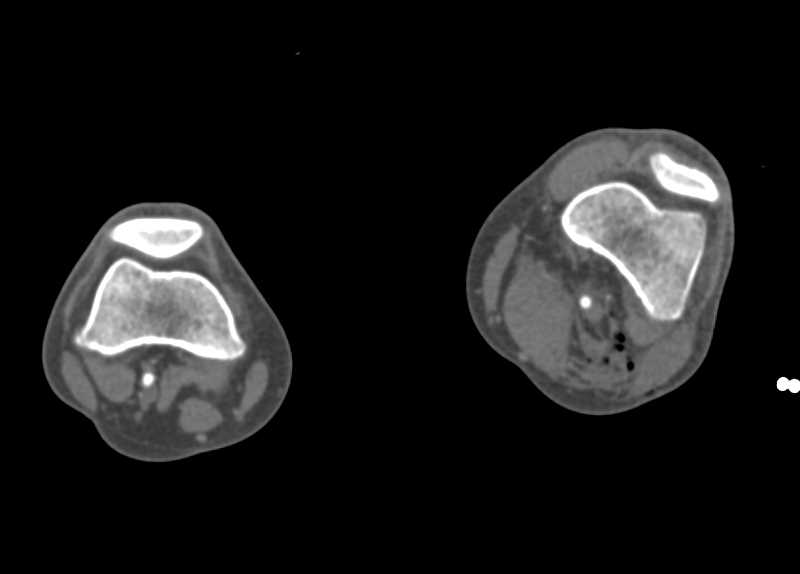

CTA Runoff with Peripheral Vascular Disease